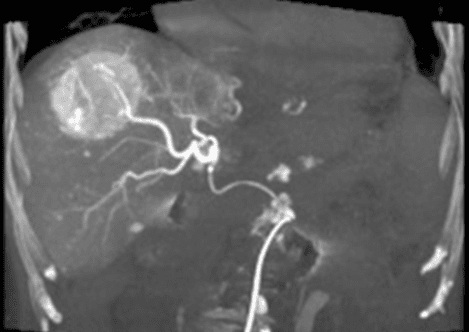

In the image above, a catheter is positioned in the hepatic artery and x-ray dye injected showing the large liver tumor at the top right of the image. The Interventional Radiologist will block the blood supply and deliver high dose chemotherapy at the same time to kill the tumor.

Chemoembolization delivers a high dose of cancer-killing drug (chemotherapy) directly to the organ while depriving the tumor of its blood supply by blocking, or embolizing, the arteries feeding the tumor. The interventional radiologist threads a catheter up the femoral artery in the groin into the blood vessels supplying the liver tumor. By blocking the blood flow to the tumor, a higher dose of chemotherapy drug can be used. This allows less of the drug to circulate to the healthy cells in the body. An overnight hospital stay is required, and most patients can go home the following morning. Patients typically have lower than normal energy levels for about week or two afterwards.